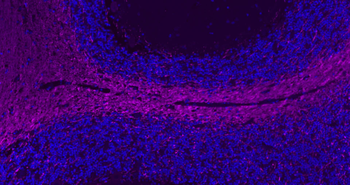

Paraformaldehyde-fixed, paraffin embedded Human Cerebellum, Antigen retrieval by boiling in sodium citrate buffer (pH6.0) for 15 min, Antibody incubation with MBP Polyclonal Antibody, Unconjugated (orb783422) at 1:200 overnight at 4°C. Followed by conjugated Goat Anti-Rabbit IgG antibody (Purple, orb868605), DAPI (blue) was used to stain the cell nuclei.